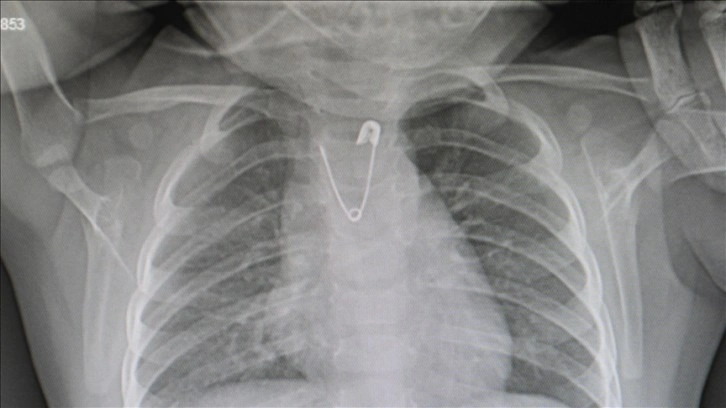

Ankara'da, yakasında bulunan çengelli iğneyi ucu açık bir şekilde yutan 10 aylık kız bebek, getirildiği Ankara Eğitim ve Araştırma Hastanesinde yapılan operasyonla kurtarıldı.

Çengelli iğne yutan 10 aylık bebek zamanında müdahaleyle kurtuldu

Bebeğin operasyonunu gerçekleştiren Ankara Eğitim ve Araştırma Hastanesi Çocuk Cerrahisi Uzmanı Doç. Dr. Çalışkan, AA muhabirine yaptığı açıklamada, toplumda bebeklere, nazar boncukları, altın, bazı dualar, şifalı olduğu düşünülen taşlar, kolye ve bilekliklerin takıldığına işaret etti.

Ancak bu nesneleri bebeklerin yutmasının ciddi riskleri de ortaya çıkardığını vurgulayan Çalışkan, ailelere, küçük çocuklarını mümkün olduğunca yabancı cisimlerden uzak tutmaları gerektiği uyarısında bulundu.

Çalışkan, "3 yaşın altındaki hiçbir çocukta, üzerinde taşıyabileceği nazar boncuğu, doğal taşlardan kolye, küpe gibi nesnelerin bulunmaması gerekiyor. Çünkü çocuklar küçük boyutlu yabancı cisimleri tanımak için ağızlarına atabiliyor ve yutma sonucu bu nesneler soluk borularına kaçabiliyor." dedi.